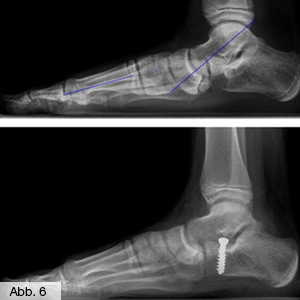

Knick-Senkfuß

Dies ist eine typische Deformität des Rückfußes (Abb. 5). Im Allgemeinen verursacht er keine Beschwerden oder es kann durch Einlagen zumindest eine Verschlimmerung verhindert werden. In schweren Fällen kommt es zu Belastungsschmerzen oder zum Hervortreten eines Knochens (Kahnbein) an der Innenseite des Fußes.

Bei Kindern ist eine operative Therapie dann recht einfach: durch eine so genannte Arthorise (Calcaneus-Stop-Schraube, Abb. 6) kann ein weiteres Absinken des Fußgewölbes gestoppt werden und das Gewölbe normalisiert sich bis zur Aufrichtung. Dieser einfache Eingriff kann an beiden Füßen gleichzeitig durchgeführt werden und erfordert einen nur ein- bis zweitägigen stationären Aufenthalt.

Bild Orthopädie Fuß Knicksenkfuss

Bild Orthopädie Fuß Calcaneusstopschraube